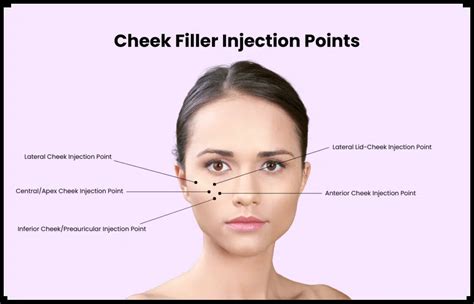

- Comprehensive facial analysis to determine optimal injection points

Multiple techniques can be employed for preauricular region filler placement, each designed to address specific aesthetic concerns:

Linear Threading Technique

The linear threading method involves carefully inserting the needle parallel to skin surface, creating smooth, uniform product distribution. This approach minimizes trauma and ensures more natural-looking results.

Micro-Droplet Technique

Practitioners may utilize micro-droplet injection for precise volume enhancement, allowing incremental product placement with minimal risk of overcorrection.